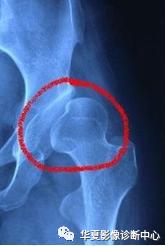

6. Shenton线:

正常闭孔上缘弧形线与股骨颈内侧弧形线相连在一个抛物线上,称为Shenton线,髋脱位、半脱位病例,此线完整性消失。

7.外侧线(Calve线)

外侧线(Calve线)即髂翼的外侧面与股骨颈外侧面的弧形连线,正常为连续的。